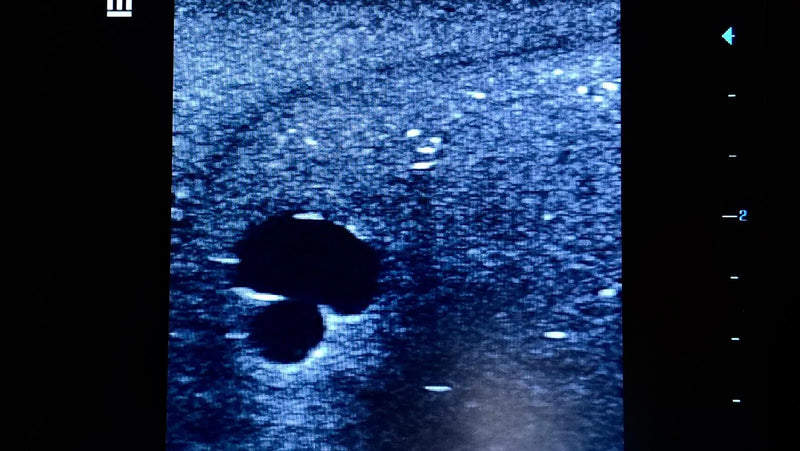

Thiết bị huấn luyện đơn giản, mạnh mẽ cho phép luyện tập lặp đi lặp lại kỹ thuật xâm nhập dưới hướng dẫn siêu âm một cách thực tế, giúp nâng cao thành thạo máy siêu âm, khéo léo sử dụng đầu dò và nhận biết cấu trúc giải phẫu. Tất cả chỉ với việc chuẩn bị và bảo trì tối thiểu.

Máy huấn luyện siêu âm BIOTME® mô phỏng mô người thật cả về cảm giác và đặc tính phản hồi sóng siêu âm. Vết kim sẽ biến mất sau vài ngày luyện tập, tăng cường tính chân thực và tiết kiệm chi phí.

Thiết bị huấn luyện đơn giản, mạnh mẽ cho phép luyện tập lặp đi lặp lại kỹ thuật xâm nhập dưới hướng dẫn siêu âm một cách thực tế, giúp nâng cao thành thạo máy siêu âm, khéo léo sử dụng đầu dò và nhận biết cấu trúc giải phẫu. Tất cả chỉ với việc chuẩn bị và bảo trì tối thiểu.

Máy huấn luyện siêu âm BIOTME® mô phỏng mô người thật cả về cảm giác và đặc tính phản hồi sóng siêu âm. Vết kim sẽ biến mất sau vài ngày luyện tập, tăng cường tính chân thực và tiết kiệm chi phí.

Thiết bị huấn luyện đơn giản, mạnh mẽ cho phép luyện tập lặp đi lặp lại kỹ thuật xâm nhập dưới hướng dẫn siêu âm một cách thực tế, giúp nâng cao thành thạo máy siêu âm, khéo léo sử dụng đầu dò và nhận biết cấu trúc giải phẫu. Tất cả chỉ với việc chuẩn bị và bảo trì tối thiểu.

Máy huấn luyện siêu âm BIOTME® mô phỏng mô người thật cả về cảm giác và đặc tính phản hồi sóng siêu âm. Vết kim sẽ biến mất sau vài ngày luyện tập, tăng cường tính chân thực và tiết kiệm chi phí.

Thiết bị huấn luyện đơn giản, mạnh mẽ cho phép luyện tập lặp đi lặp lại kỹ thuật xâm nhập dưới hướng dẫn siêu âm một cách thực tế, giúp nâng cao thành thạo máy siêu âm, khéo léo sử dụng đầu dò và nhận biết cấu trúc giải phẫu. Tất cả chỉ với việc chuẩn bị và bảo trì tối thiểu.

Máy huấn luyện siêu âm BIOTME® mô phỏng mô người thật cả về cảm giác và đặc tính phản hồi sóng siêu âm. Vết kim sẽ biến mất sau vài ngày luyện tập, tăng cường tính chân thực và tiết kiệm chi phí.